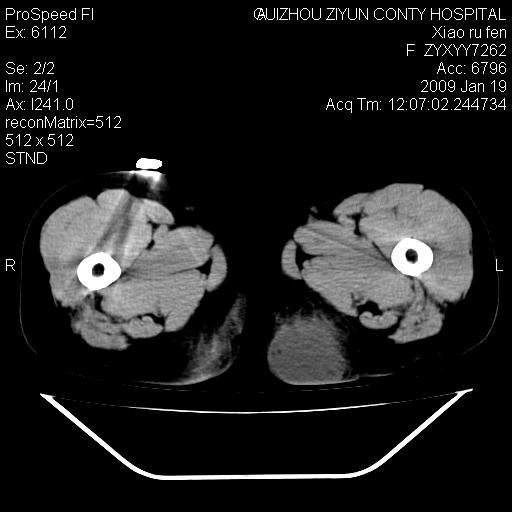

以下是引用随光逐影在2009-1-19 16:15:00的发言:[br]左侧臀部类似软组织密度肿块,性质待定(不排除肿瘤可能);建议行进一步检查。

以下是引用zbp537在2009-1-19 14:25:00的发言:[br]考虑两个诊断:1、皮脂腺囊肿伴感染。2、脓肿。[br]诊断依据:[br]1、肿块为低密度,边界较清,和皮肤相连,周围结构清晰,未见受累及。[br]2、诊断脓肿是因为其内密度不均匀,当然要结合病史,因为脓肿临床上肯定表现为红肿热痛,也希望楼主把病史提供全面些,这些便于讨论。

以下是引用zbp537在2009-1-19 14:25:00的发言:[br]考虑两个诊断:1、皮脂腺囊肿。2、脓肿。[br]诊断依据:[br]1、肿块为低密度,边界较清,和皮肤相连,周围结构清晰,未见受累及。[br]2、诊断脓肿是因为其内密度不均匀,当然要结合病史,因为脓肿临床上肯定表现为红肿热痛,也希望楼主把病史提供全面些,这些便于讨论。